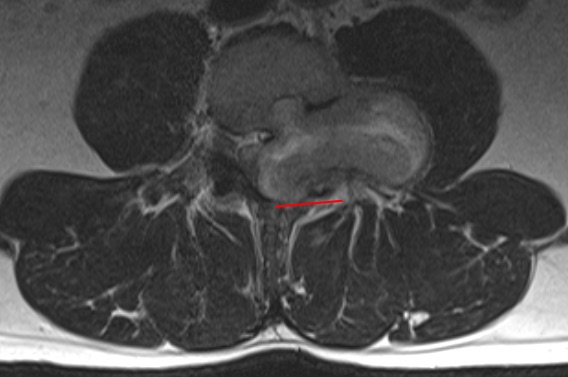

Craneal es izquierda; medial es inferior.

En esta imagen, medial es superior